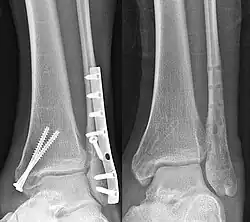

Knöchern durchbauter Sprunggelenksbruch vor und nach Metallentfernung. Beachte die Sklerosesäume

Das Osteosynthese-Material kann später entfernt werden („Metallentfernung“), dies ist aber nicht zwingend und bei einigen tief liegenden oder fest in den Knochen eingewachsenen Osteosynthesen gar nicht oder nur mit großen Schwierigkeiten möglich. Zunächst muss radiologisch ein sicheres Zusammenwachsen der Knochenfragmente festgestellt werden. Eine Entfernung ist besonders dann indiziert, wenn Schmerzen über dem Material bestehen, sich eine Muskel- oder Sehnenreizung gebildet hat, Material in ein Gelenk hinein reicht, spätere Eingriffe ermöglicht werden müssen (wie zum Beispiel Einsatz einer Endoprothese), Nerven- oder Gefäßschäden auftreten oder das Material durch die Haut drückt. Auch wenn eine Infektion vermutet wird, ist eine Entfernung notwendig.

Auf Röntgenbildern findet man nach Entfernung einer osteosynthetischen Versorgung häufig noch Verdichtungslinien (Sklerosesäume), die die ehemaligen Implantate nachzeichnen. An den Grenzflächen des spongiösen Knochens zum eingebrachten Fremdmaterial (z. B. Schraube) sklerosiert der Knochen als Anpassungsreaktion auf die lokal gesteigerte Belastung.